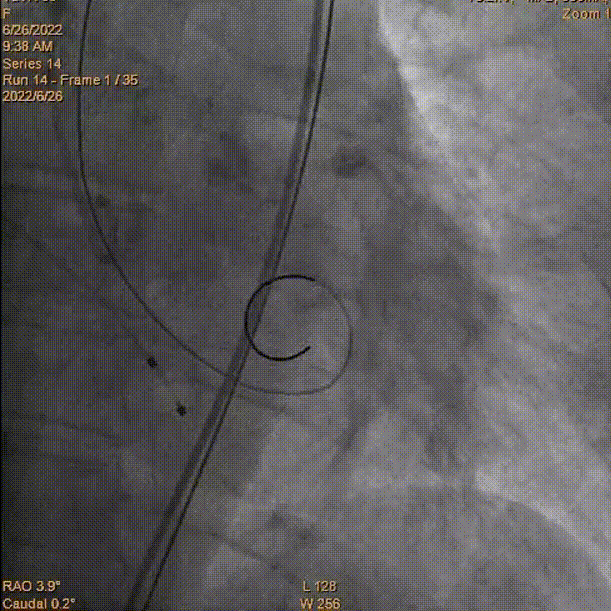

术中影像:

主动脉根部造影

瓣膜释放至工作位

完全释放到达理想状态

术后主动脉根部造影压差为8mmHg